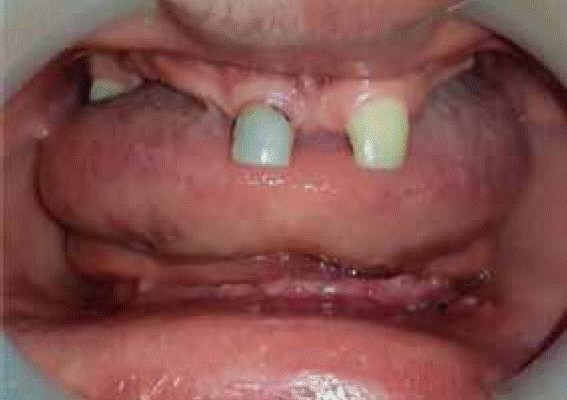

Stomatological examination revealed bone atrophy of alveolar processes in both jaws, true anodontia of teeth number: 11, 12, 13, 14, 15, 16, 18, 22, 23, 24, 25, 26, 27, 28, 31, 32, 33, 34, 35, 36, 37, 38, 41, 42, 43, 44, 45, 46, 47, 48, presence of cone-shaped, primary tooth 51 with mobility, moreover, there was presence of upper frenulum over-insertion. Alveolar ridges of upper and lower jaw were arranged as a class III according to Seibert’s classification. Mild marginal gingivitis associated to generalized dental plaque was diagnosed (Figure 2).

Radiographic examination revealed class II Seibert upper and lower ridge collapse, presence of a root remnant at the level of tooth 43, and radio-opaque areas at level of tooth 51 which were compatible with filling (Figure 3).